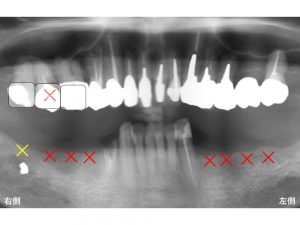

下顎の左右の奥歯が欠損している方です。

左側が4歯分欠損、

右側が3歯分欠損しています。

(下顎の右側は上の歯が親知らずまであるので、それに合わせると4歯欠損です)

上顎の右側は、親知らずまであります。